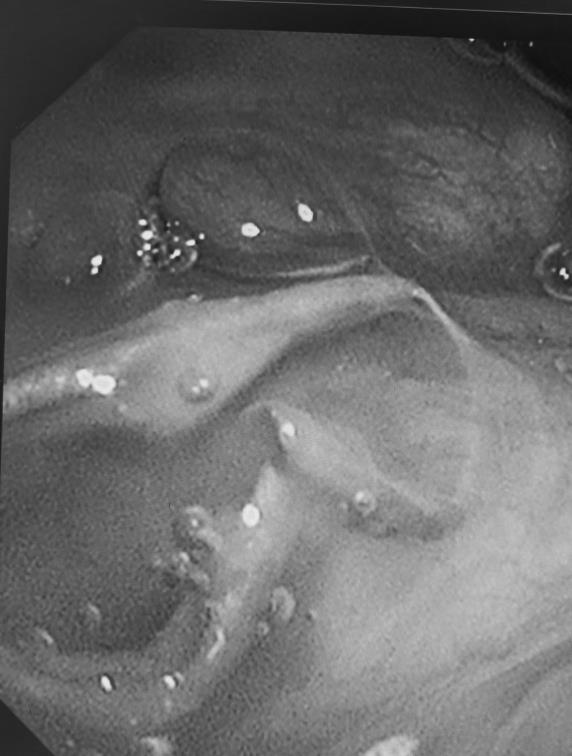

江师傅立即来到武汉市肺科医院就医。内镜中心主治医师吴鸣镝操控电子支气管镜进入江师傅 9 年前手术处理的区域检查,意外发现了一个蜷缩的钉子。

肺上怎么会有钉子?仔细研究发现,这是一枚手术钉。9 年前,切除右下肺叶时,医生用多枚手术钉缝合了切口。理想状态下,这些钉子,应该随着时间的推移,逐步与切口吻合,融为一体。如今「脱岗」,可能与爹爹某次咳嗽时,用力过大有关。

吴鸣镝立即通过内镜工具将钉子取出。